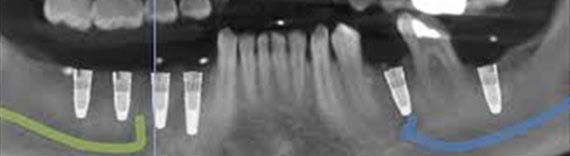

Centre for Oral Implantology

Dental implants are the most sought after treatment modality these days & to keep out young professionals updated with technology, the institute has a well equipped Implantology clinic for training the students as well as implant courses with Bioner Dental Implants Spain, is conducted for improvised and advanced student learning.